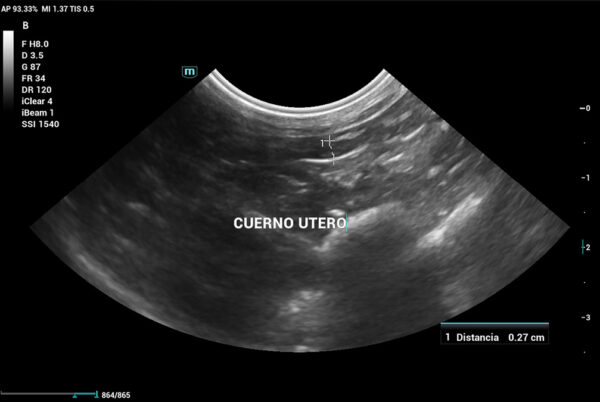

Se realiza ecografía abdominal, que evidencia que aún cuenta con cuernos uterinos (imagen 6), lo que confirma la ovariectomía (no ovariohisterectomía). Por este motivo, se decide enviar una muestra de plasma sanguíneo a un laboratorio externo para evaluar los niveles de 17β-estradiol, dado que en ecografía no se logra distinguir con claridad un remanente ovárico.

En conejas esterilizadas o con sospecha de remanente ovárico, valores de 17β-estradiol por encima de 10 – 20 pg/mL pueden indicar la presencia de tejido ovárico funcional residual (debería presentar aproximadamente la misma concentración que un conejo macho). En el caso de esta coneja, el resultado fue de 62 pg/mL, lo cual confirma la presencia de remanente ovárico, dado que hay producción de estrógenos. En este caso, fue suficiente con la medición de estradiol para confirmar el diagnóstico, aunque en otras ocasiones podríamos utilizar la medición de hormona antimulleriana como alternativa.

Además de las pruebas descritas, y dado que los tutores comentaban que la coneja dejaba de practicar la cecotrofia en algunos momentos, también se realiza un estudio radiográfico de columna, en el cual no existen alteraciones de relevancia que justifiquen un dolor de columna que pueda explicar la ausencia de cecotrofia. Ante el resultado de todas las pruebas realizadas, se decide llevar a cabo una histerectomía.

En las pacientes sometidas a ovariectomía sin histerectomía, debemos tener en cuenta que aún existe riesgo de que padezcan algún tipo de patología uterina que pueda desarrollarse sin ovarios, así como actividad uterina residual, persistencia de conductas hormonales y de síndrome del remanente ovárico, como en el caso presentado.